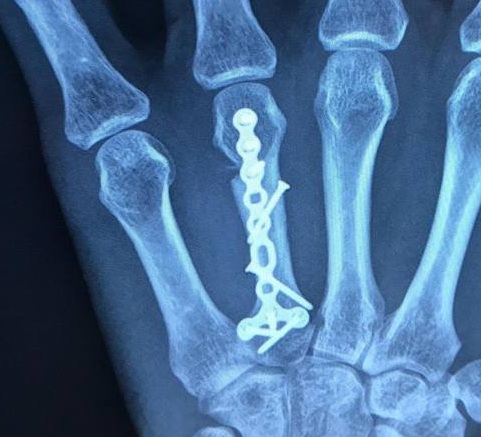

プレート固定

中手骨骨折に対する最も安定した固定法はプレート固定です。しかし、プレートを骨に装着させるにはより広範囲の切開が必要となり、術後の硬直が増加する可能性があります。インプラント設置のための背側切開は、伸筋腱の炎症や癒着につながる可能性があります。粉砕転位骨折では、プレートとスクリュー構造が内固定に最適な選択肢となる場合があります。プレートは、明らかな欠損がある場合でも中手骨の長さを維持できます。最近の研究では、合併症の発生率は様々ですが、良好な機能が得られることが示されています。プレートの突出は、硬直に寄与する可動域低下の一因となります。インプラントの技術革新により、プレートは解剖学的形態に合わせてより薄型化されています。